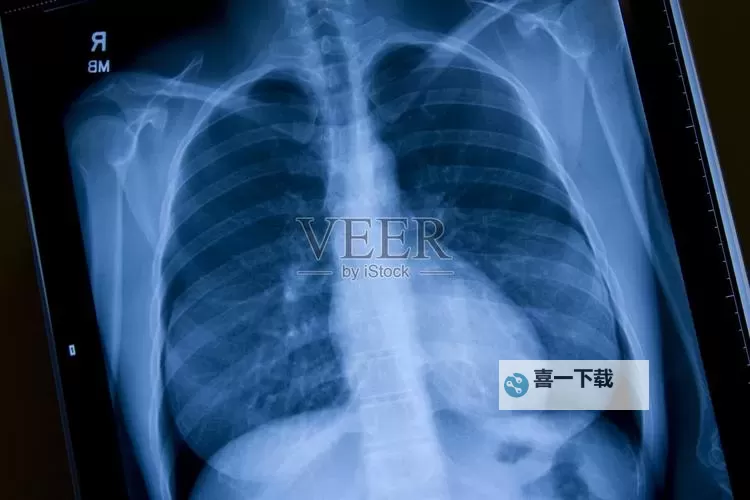

在医学检查中,胸部X光片是判断肺部和心脏健康状况的重要工具。一个高质量、透明的曝光率可以帮助医生快速准确地了解患者的胸腔状况,从而制定最适合的治疗方案。宣传中提到“100%胸片曝光率”,意味着每一份胸片都能被完整、清晰地展示,没有遗漏或模糊部分。这种全面的曝光效果,不仅提升了诊断的准确性,也为患者的健康安全提供了有力保障。

在确诊肺炎、肺结核、肿瘤等疾病时,高清晰度的胸片起到了关键作用。高曝光率确保病变、异常结构得以完整呈现,无论是微小的阴影,还是复杂的结构变化,都能被细致捕捉。这对于早期筛查和诊断具有重要意义,有助于及时发现潜在健康问题,避免错诊漏诊的风险。对于患者而言,能够以更高的准确率获得诊断结果,也意味着可以更快进入相应的治疗阶段,缩短康复时间,减少并发症的发生可能性。